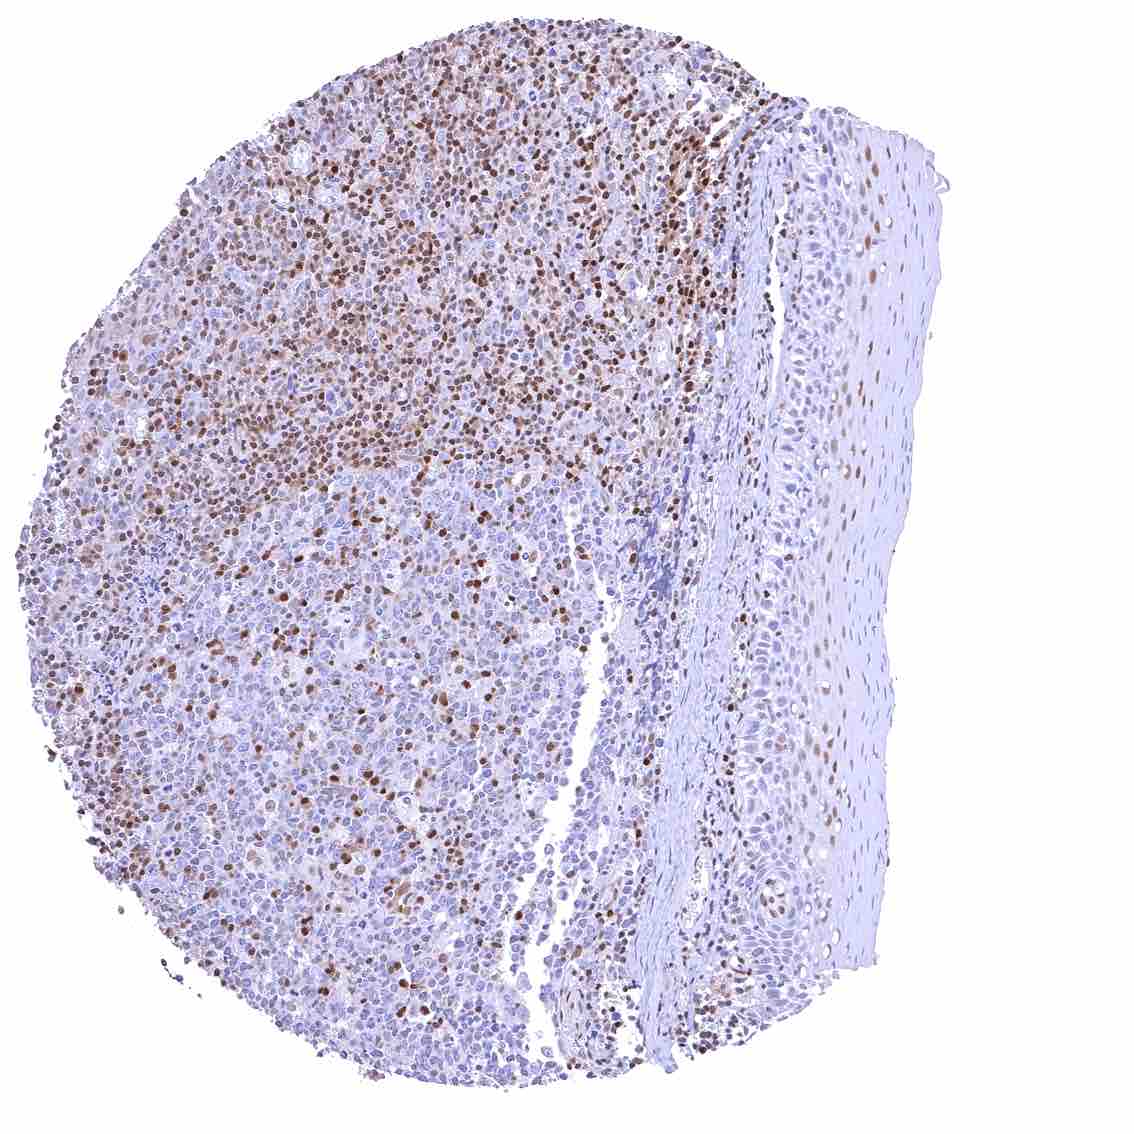

Lymph node – Strong nuclear p27 staining of a significant subset of cells, especially in the interfollicular area.